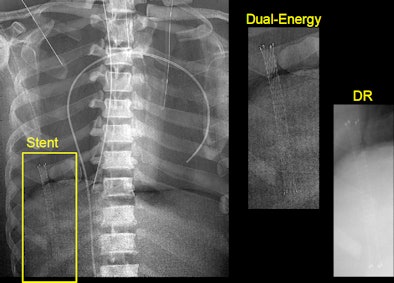

![]() |

| Dual-energy imaging shows the placement of a stent in a cadaver more clearly than the stent can be seen by digital radiography. |